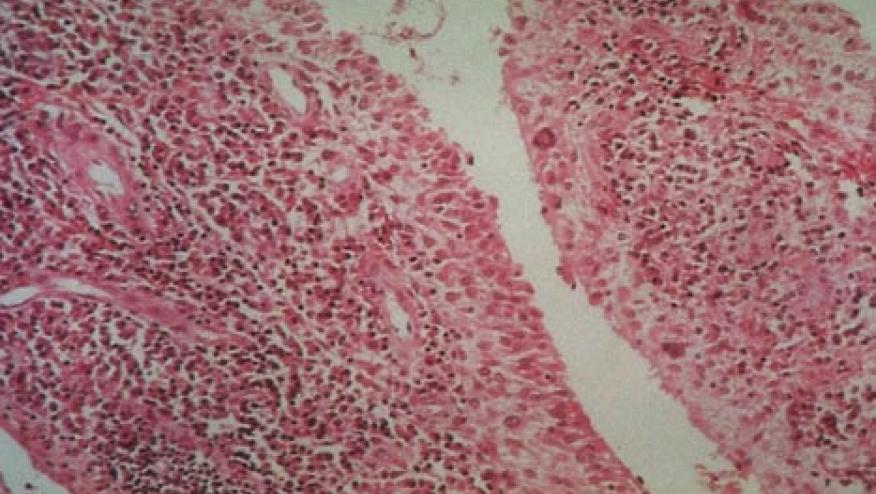

The AMP:RA/SLE Network collected inflamed synovial tissue from 70 rheumatoid arthritis (RA) patients with RA from multiple centers in the US and UK and usied multi-modal single-cell RNA-sequencing and surface protein data coupled with histology of synovial tissue to build single-cell atlas of RA synovial tissue that includes more than 314,000 cells. They classified CTAPs on the basis of relatively enriched cell types:

They identified six CTAP groups each characterized by selectively enriched cell states, that may be correlated with cytokines, risk genes, histology and serology. The authors suggest that CTAPs are dynamic and can predict treatment response, highlighting the clinical utility of classifying rheumatoid arthritis synovial phenotypes.